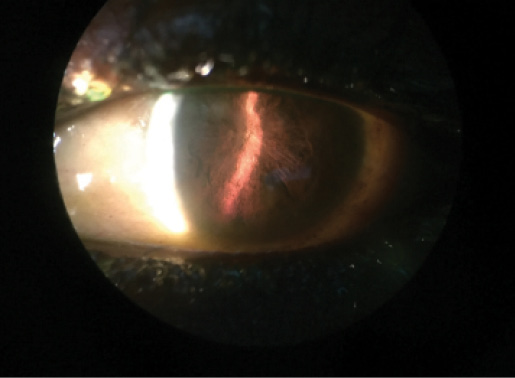

Figure 1. Slit-lamp photograph shows complete pupillary seclusion in an EVD survivor with chronic uveitis and hypotony.

In West Africa, blindness has been observed in some EVD survivors due to structural complications associated with uveitis, including cataract, hypotony, tractional retinal detachment (TRD), and phthisis bulbi (Figure 1). It is not known whether invasive ophthalmic procedures can be safely performed for visually significant cataract and TRD in these patients, given the risk of EBOV persistence in ocular fluids. Studies are under way to address these questions. The answers will be important in light of the number of patients with uveitis who require surgical care for cataract and vitreoretinal disease.11,12